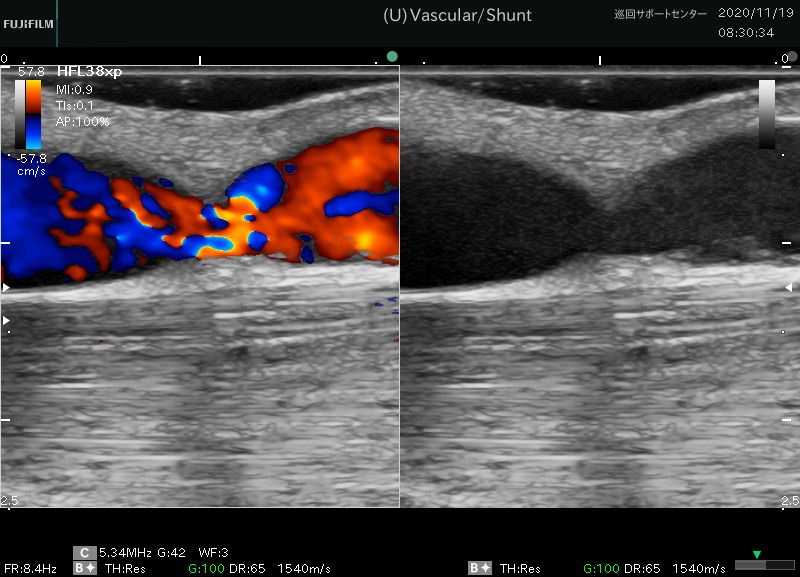

画像検査により水頭症の診断を確認できます。超音波、 CT スキャン、およびMRI スキャンにより、医師は脳内の空洞や組織を観察できます。検査により、脳の領域に通常よりも多くの体液が含まれているかどうかがわかります。